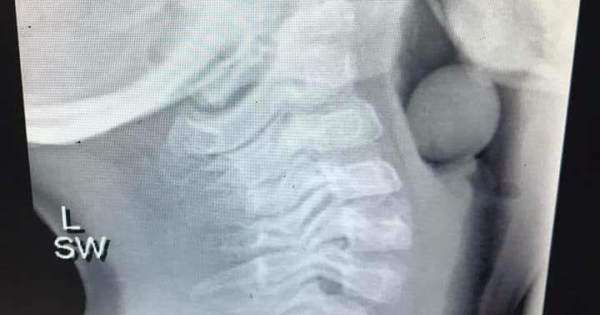

Мајка сподели рендгенска снимка од зрно грозје заглавено во грлото на детенце за да ги предупреди родителите за потенцијалната опасност на ова овошје.

Анџела Хендерсон од Австралија, креаторка на блогот Finlee and Me, на својот профил на Facebook објави фотографија преземена од педијатар за да им ја зголеми свеста на родителите за можноста од задушување со грозје кај децата. Рендгенската снимка е од 5-годишно момче.

Рендгенска снимка

Знаете ли од што е оваа рендгенска снимка? Од грозје!

Зрно грозје заглавено во дишните патишта на 5-годишно дете денес.

Оваа слатка душичка мораше да биде оперирана со генерална анестезија за да ѝ биде отстрането зрното. Тој имаше среќа што дел од неговите дишни патишта остана отворен, во спротивно ќе имаше лош исход.